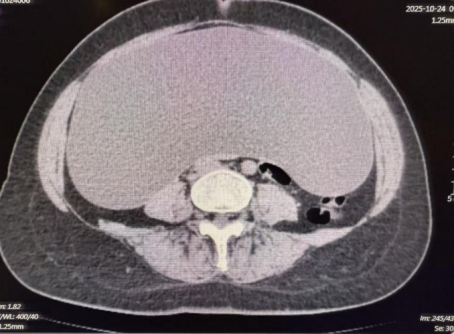

一位发现腹腔中出现巨大占位性病变的患者来院就诊,经影像学检查发展腹腔内囊性低密度阴影面积高达45cm×35cm×14cm,对周围脏器形成严重压迫,手术难度极高。王兆太主任团队经周密讨论,决定采用腹腔镜微创技术治疗。术中,团队先分阶段穿刺引流7500毫升囊内液体,为操作创造空间,随后发现囊肿与右侧卵巢、圆韧带关系密切,立即启动多学科协作,邀请妇科范桂芬主任现场指导,精准分离粘连组织、保护重要结构。手术顺利完成,囊肿被完整切除,术中出血量少,患者术后生命体征平稳,快速康复。